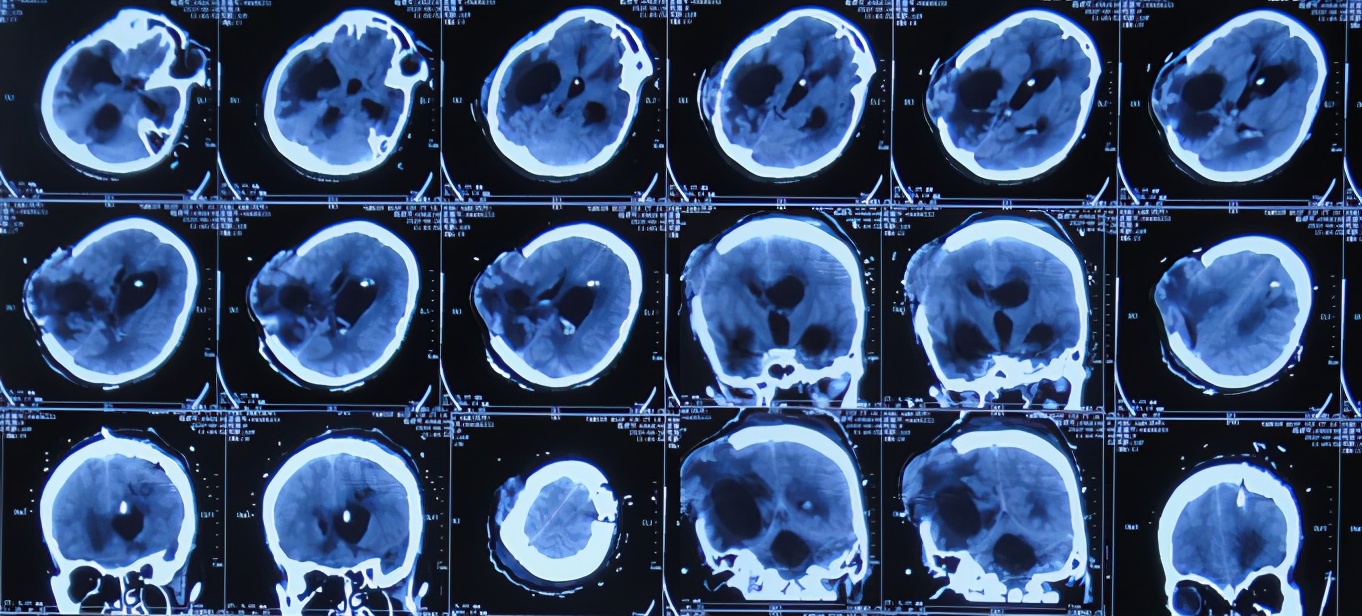

患者于2020年4月2日,在公司上班时突发头痛呕吐,急诊至陕西省西安市某二级医院,急诊查头颅CT检查示右顶叶脑出血破入脑室( 图-1 ),全脑血管造影示脑血管畸形(片子丢失);进行了开颅脑血管畸形切除术+去骨板减压术,术中留置引流外管;术后当天转入ICU继续治疗。

图-1: 2020年4月2日头颅CT